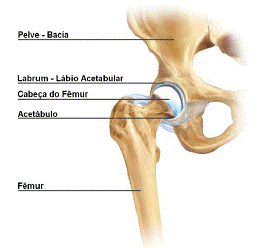

Lesões e doenças do quadril podem ser extremamente incapacitantes. Muitas estruturas podem refletir dor no quadril e na sintomas são muitas vezes confusos para o paciente e desafiadores não estando aparente para o paciente. As áreas do quadril e pélvica são também locais comuns para dor referida. O fisioterapeuta tem um papel importante na identificação do local lesionado, ou que está precisando de tratamento.

Lesões do Lábio Acetabular (Lesões do Labrum) são lesões que ocorrem no quadril. Envolvem a ruptura da cartilagem que recobre a borda do acetábulo. Acetábulo é a concavidade onde o fêmur encaixa. Ou seja, é o local onde o fêmur (osso da coxa) se articula com a bacia.